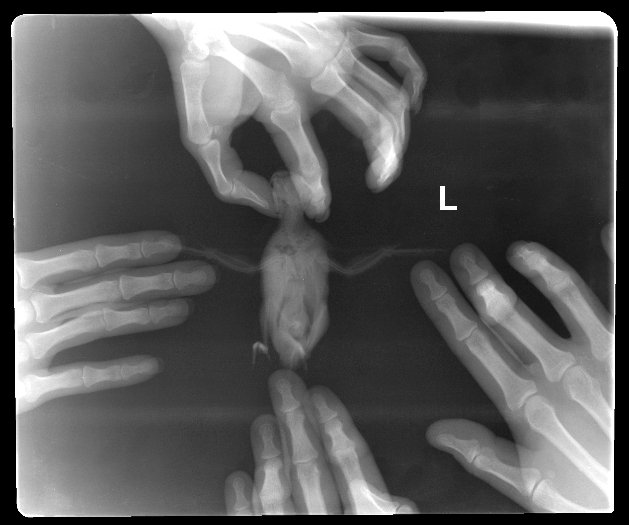

6. Здравствуйте, имеем волнистого попугая с новообразованием семенников. Рентген и заключение врача прикладываю. Читала про такую схему: преднизолон/мелоксикам/ригевидон. Для нас актуально? @Zosia